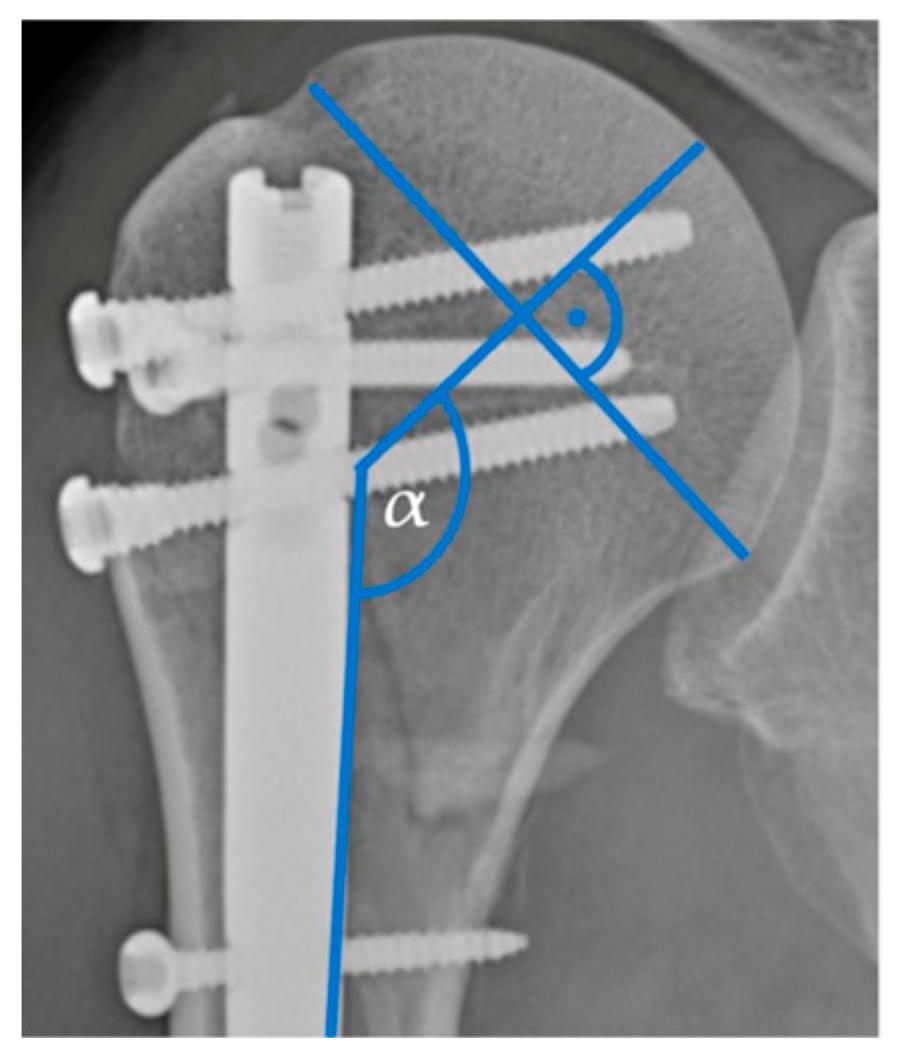

The pre- and postoperative radiographic imaging was assessed using Picture Archiving and Communication System software (Version: Ashvins 2017 Build 1637), which involved the analysis of plain radiographic images or computed tomography (CT) scans. Fractures were classified based on the number of fractured parts and according to the Neer classification system [16]. The analysis also focused on assessing the postoperative anatomical reposition of the fractures and the pre- and postoperative head–shaft angle (HSA) (Figure 1).

Figure 1.

Head–shaft angle.